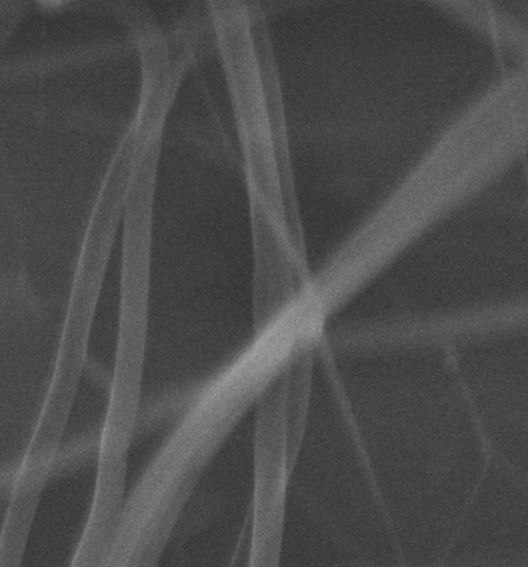

Morphology, size and size distribution of the nanofibres

Morphology analysis was adapted from Aytac et al. (2019) [38]. The SEM analysis was conducted to detect electrospun nanofibers' fibre shape and diameter. The electrospun nanofibres from 18 runs were investigated individually by SEM (FEI, quanta 450, Czech). Images revealed the morphology of resultant nanofibers and measured their diameters in nanometres. The average number of records was calculated using a standard deviation estimation. The setting of the SEM machine was conducted on voltage 25.00 kv, magnification 23624 and width (8.3-9.3 mm).

Results of the SEM analysis are listed in table 2, with a wide range of fibre diameters starting from 87.2 nm (run 13) to 2500 nm (run 18). Run 18 did not produce true nanofibers due to the deficient concentration of PVA. The statistical analysis revealed that the effect of each polymer (factor) on the diameter size of the electrospun nanofiber was vast. Therefore, there is a correlation between factors A, B and C and fibre diameter as expressed in equation 5.

Fig. 3: Nanofibres SEM images with nanofiber diameter frequencies. The PVA, PEO and HPMC were symbolised as V, E and P. Data are given in mean±SD, n=3

The morphology of nanofibers would be affected by device parameters such as flow rate, voltage and distance from the collector. Also, nanofibres' properties could be changed due to temperature and humidity. The bead formation appears with a low concentration of PVA (run 2) or a high concentration of PEO and HPMC (runs 6 and 11), as shown in fig. 3. Therefore, increasing PVA concentration leads to beads' disappearance and smooth fibres' formation. Nageeb El-Helaly (2021) and Silva J. A. et al. (2021) reported similar results [47, 48]. Kalluriet al.(2021)[49] studied the relationship between the fibre diameter, bead diameter and flow rate. Thus, they concluded that better fibre uniformity and bead formation were needed at a high flow rate. These results appear clearly in run two and run six and agree with Silva et al.(2021) results [50], who reported that only the concentration of PVA (≥ 15%) could produce uniform nanofibers when using the lower molecular weight of PVA (67,000). Fibre diameter of 15% PVA and more appeared to be in the range 87.11 to 252.5 nm with uniform fibres and disappearance of beads except in run 6, where the beads appear due to increasing the concentration of HPMC as highlighted by Gripet al. (2018) [46].